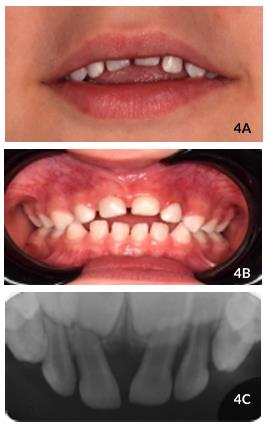

In the first appointment, clinical and radiographic examinationswere performed. Was observed swollen gums in the region of the upper incisors, was observed tooth #61 was intruded, with a third of the crown visible (grade II) and mild intrusion of tooth #62, with more than a third of the crown visible (grade I) (Figure 1A ).

Radiographically, (modified periapical anterior and Fazzi’s lateral radiograph), teeth #61 and #62, without fracture of the bone plate and injury to the germs of

the permanent teeth (Figures 1B and 2). The treatment of choice was to wait for spontaneous teeth re-eruption.

On clinical examination after 7 days, redness and swelling of the gingival mucosa was observed. There was no mobility #61 and #62, and #61 with a third of the crown visible. On clinical and radiographic examination after two weeks, it was possible to observe a mild re-eruption of the dental elements (Figures 3A and 4B).

After 60 days, tooth #61 almost completely re-erupted and #62 completely re-erupted (Figures 4A and 4B), without color change,

Figures 3A y 3B Clinical and radiographic aspects after two weeks following trauma showing the beginning of the re-eruption process.

complaints of pain, inflammation or fistula. In addition, the gums looked healthy. Radiographically, there is no observed presence of periapical and periodontal lesions (Figure 4C). On the 8 months follow-up, it was found that tooth #61 re erupted satisfactorily, despite being slightly above the line of occlusion and the patient presenting an anterior open bite. Absence of gingival inflammation, fistula or pain was

Figures 4A,4B y 4C Clinical and radiographic aspects after 2 months following trauma with complete re- eruption of teeth.